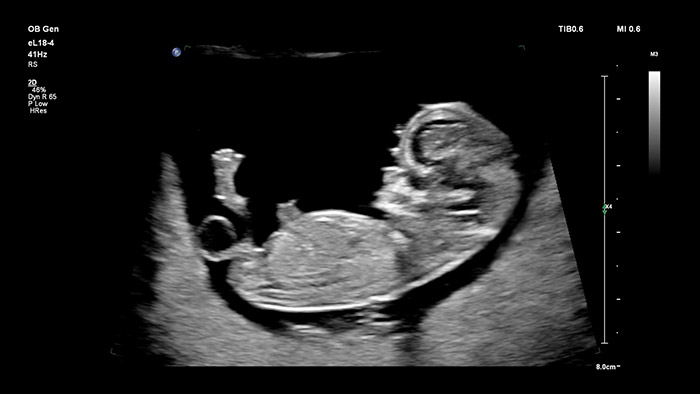

The Philips eL18-4 transducer with Microflow Imaging breaks down barriers with high resolution 2D imaging and ultra-sensitive blood flow detection to evaluate overall fetal health in the early stages of pregnancy—where superb resolution and diagnostic confidence are critical. Highly versatile, uniquely designed for OB, V9-2 transducer uses the power of PureWave crystal technology to provide superb 2D and 3D imaging while remaining lightweight for its class.